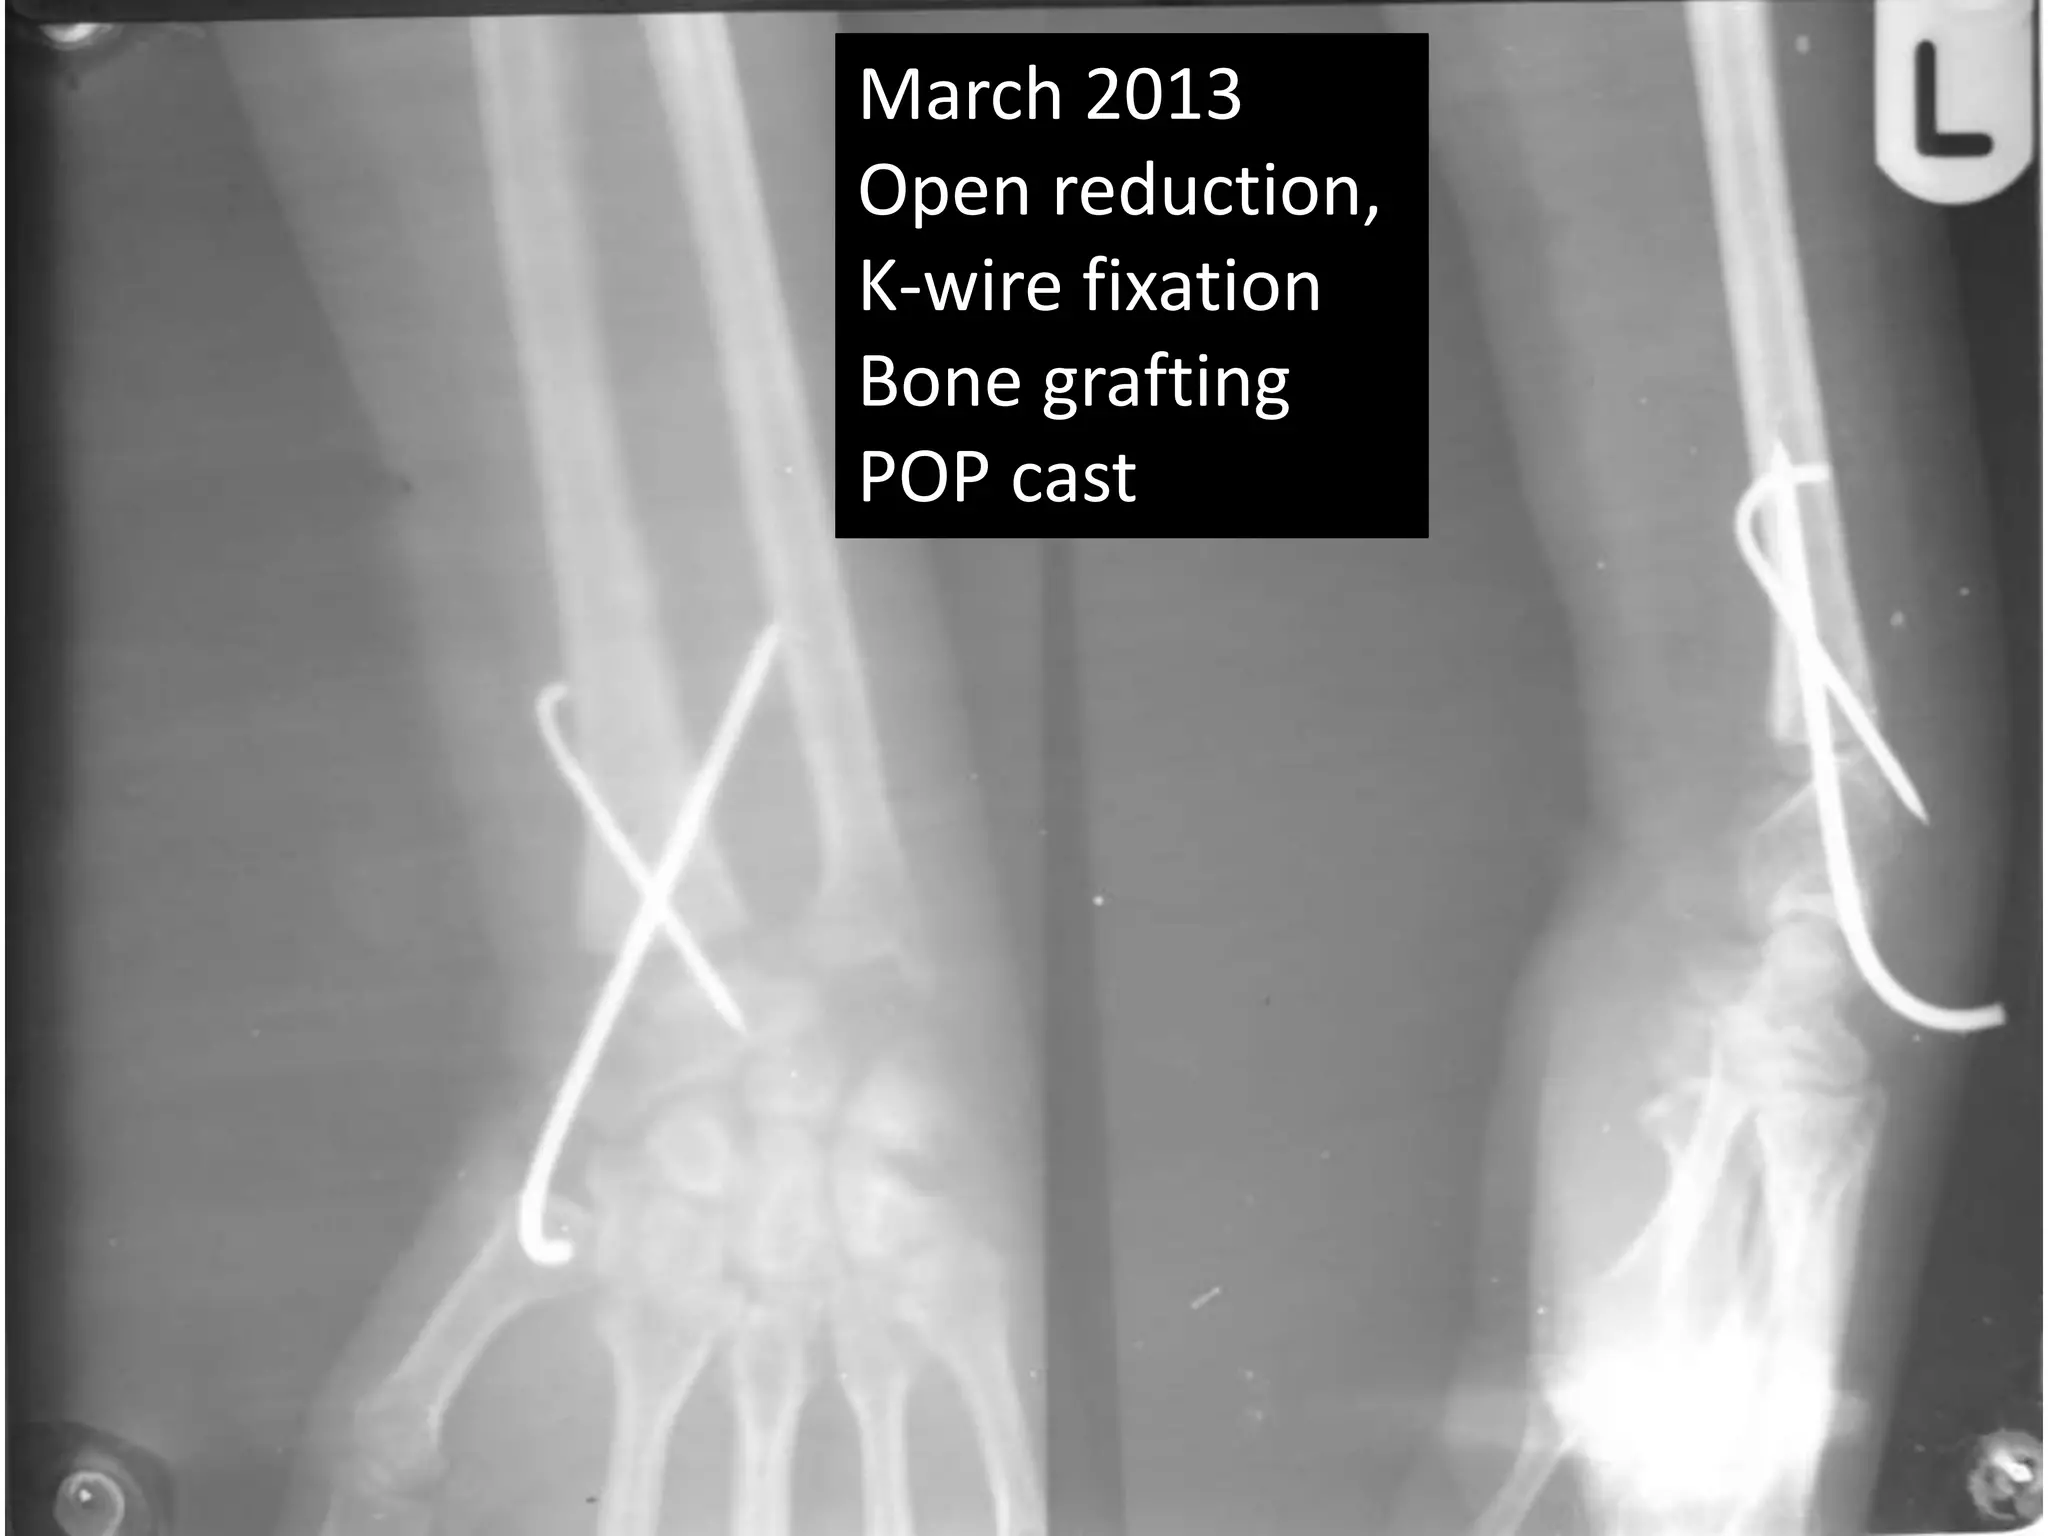

March 2013

Open reduction,

K-wire fixation

Bone grafting

POP cast

March 2013 Openreduction, K-wire fixation Bone grafting POP cast